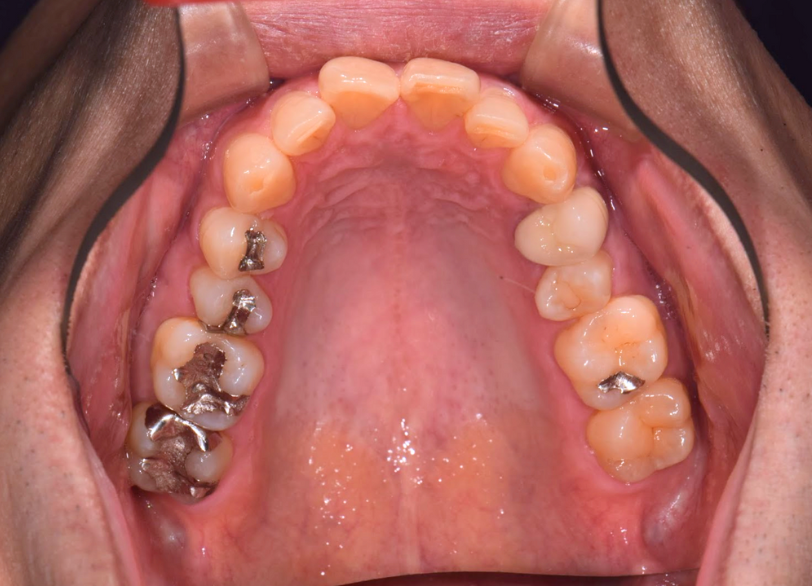

2025/04/22 セレック

MY2619様

通院時年齢 53歳

性別 女性

通院目的 虫歯なのか、たまに痛むが歯科恐怖症で怖い

診断 ①重度歯周炎

②う根面からの歯髄近接う蝕

処置内容 (または主訴) ①歯周治療(SRPまで)

②MTAセメントを用いた歯髄温存慮方法からセレックにて修復

通院期間 ①1年(歯周病治療)

②セレック1日

費用

①重度歯周炎 保険請求の範囲内

②う根面からの歯髄近接う蝕 MTAおよび一次的神経保護44,000円

セレック77,000円

リスク・副作用

①歯周病は定期的なメンテナンスが必要で歯ブラシを怠ると根面う蝕や歯周病の再発があります。

②神経を温存しておりますが、神経症状が生じた場合には抜髄と言って神経を除かなくてはならないことがあります。

処置後知覚過敏が生じることがあります。